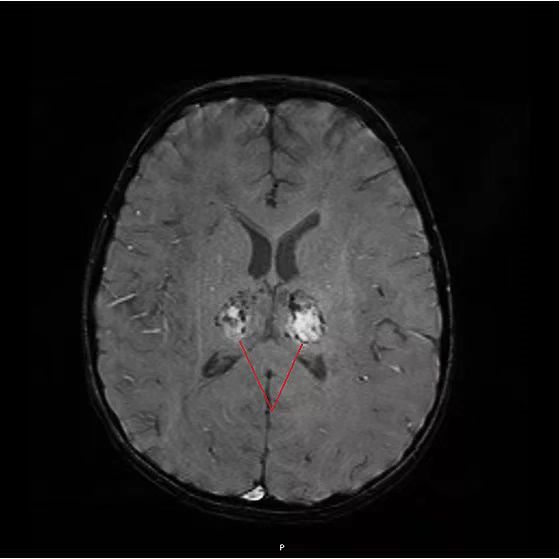

核磁共振检查发现:她的脑部发现丘脑对称性病变,这是典型的急性坏死性脑病!进一步检查后,“祸首”被揪了出来: 乙型流感病毒 。

悦悦脑部出现病灶(图源:深圳市儿童医院)